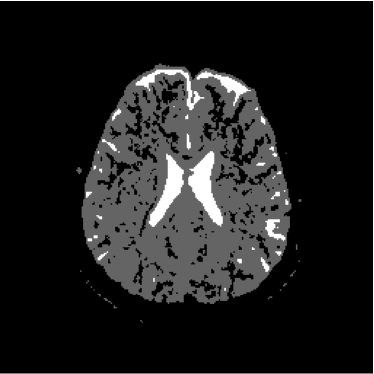

Figure 13 shows the training set mounted on the 13th slice of the volume of ADC maps. Figures 14 and 15 show the ground truth volume and the 13th slice, respectively.

Refer to caption

Figure 14: Ground truth image (13th slice) generated by polynomial net classification